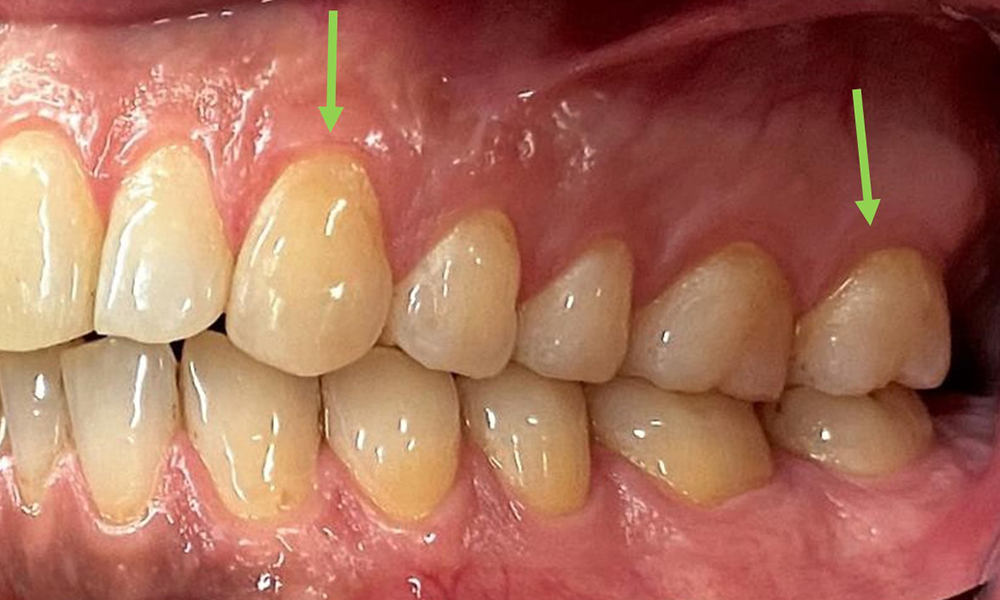

Vue rapprochée des dents

Fig. 5: Vue rapprochée des dents 45 à 47. Les flèches vertes montrent l'attrition dentaire et les érosions des cuspides buccales avec perte partielle d'émail., © Dr R. Krapf